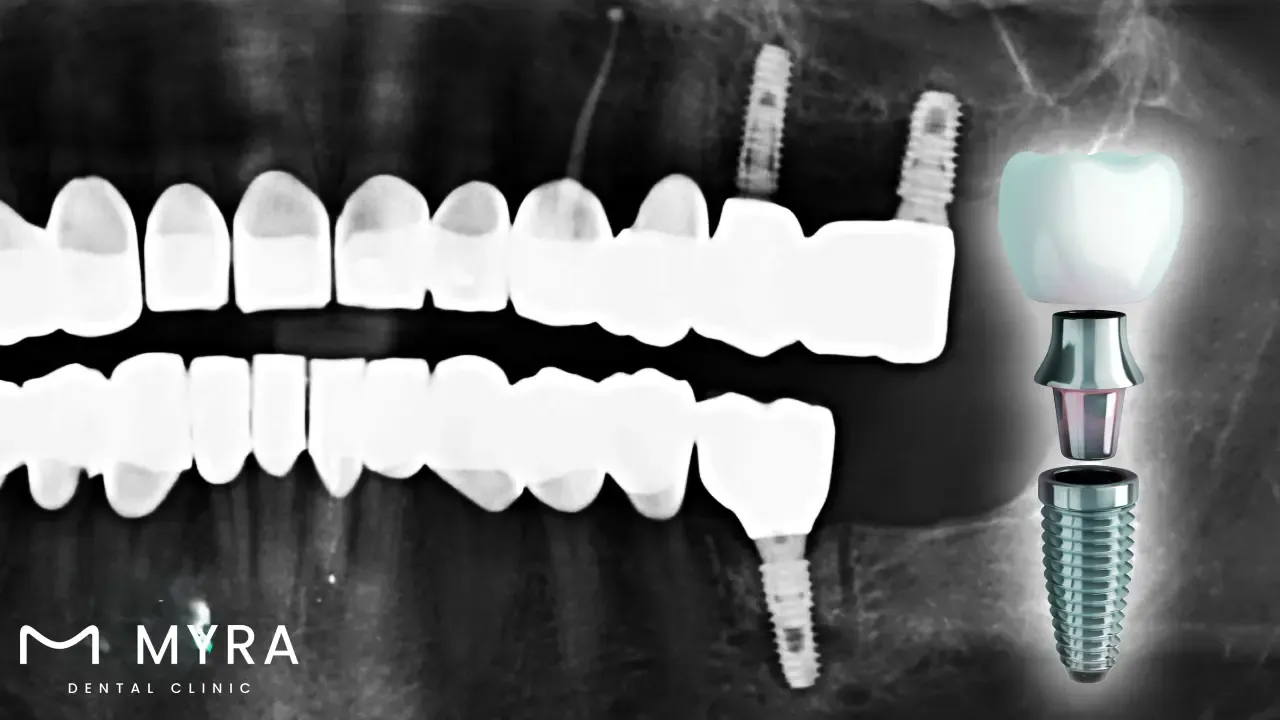

Titanium implants are common ways of restoring lost teeth. Titanium Implants are made up of a titanium post that is surgically placed into the jawbone to replace the missing tooth's root. Titanium is selected for its biocompatibility, strength, and longevity, making it an excellent choice for dental implants. The titanium post undergoes osseointegration, which merges with the surrounding bone to form a stable and permanent foundation for the dental prosthetic, such as a crown, bridge, or denture. The primary benefits of titanium dental implants are their strength and ability to maintain jawbone health. They stimulate bone and prevent bone loss by replicating the natural tooth root, which helps keep the face's structure and look.

Titanium is a critical component in dental implants, serving as the fundamental element of the implant root. The titanium part of a dental implant is a thin screw-like post that is surgically placed into the jawbone to replace a missing tooth's root. Titanium's inherent features, including biocompatibility, strength, and corrosion resistance, ensure that the implant endures the daily stresses of chewing and biting, providing a long-term solution for tooth replacement.

Place the implant. The dental implantation process takes place with local anaesthesia. The oral surgeon or implantologist makes an incision in the gum tissue to expose the jawbone before drilling a small hole for the titanium implant. The implant is gently inserted into the bone, like “teeth screws” in the gum, and the gum tissue is sutured together around it.

Put in the abutment. The implant requires a second surgical procedure to be attached to the bone after osseointegration is complete. The abutment connects the implant to the dental restoration.

Begin the restoration process. A bespoke dental restoration, like a crown, bridge, or denture, is fabricated after the gums have healed around the abutment. The restoration is intended to match the natural teeth' shape, size, and colour, resulting in a seamless and natural appearance.